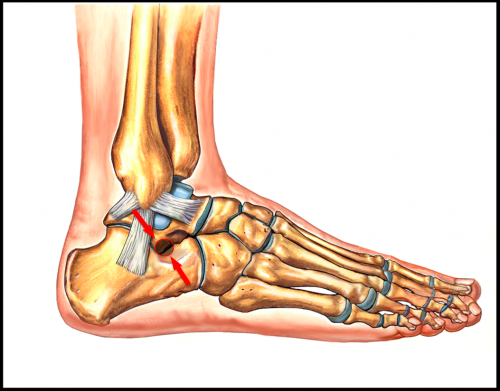

Sinus Tarsi Syndrome (STS) may be a condition that affects the surface of the foot and ankle. For more information on Sinus Tarsi Syndrome Causes, Symptom and Treatment.

Supportive crepe bandage can be applied to restrict ankle movement.Other helpful physiotherapy modalities and techniques can be used to reduce pain.Mobilization of the joints of the ankle and foot especially the subtalar joint is an important part of treatment.

A specialized manual therapist should be able to mobilizations the foot and ankle joint appropriately for sinus tarsi syndrome.Correction of biomechanical problems such as overpronation should be done.

This may help relieve the narrowing of the sinus tarsi canal.